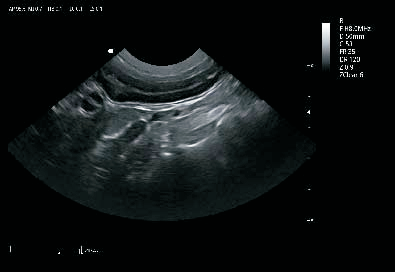

卓越的图像质量